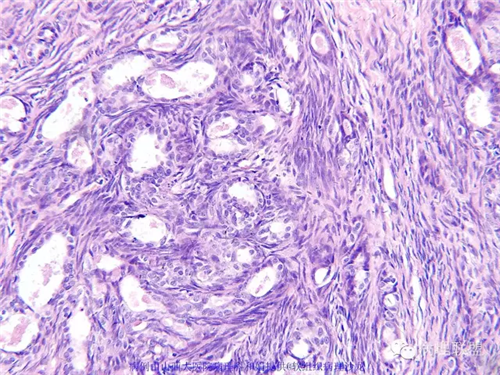

M,57岁,右膝关节外侧皮下肿物10余年,活动度好。

本例形态学上是非常典型的双相型滑膜肉瘤,滑膜肉瘤临床上大部分表现为生长缓慢的肿瘤。以青壮年多见,主要发生于四肢大关节附近,也可见于其他少见部位,如肺、肾等实质器官,形态学分为5种类型:单相纤维型、单相上皮型、双相型、低分化梭形细胞型和小细胞型。有文献报道个别患者有长达20年的病史。